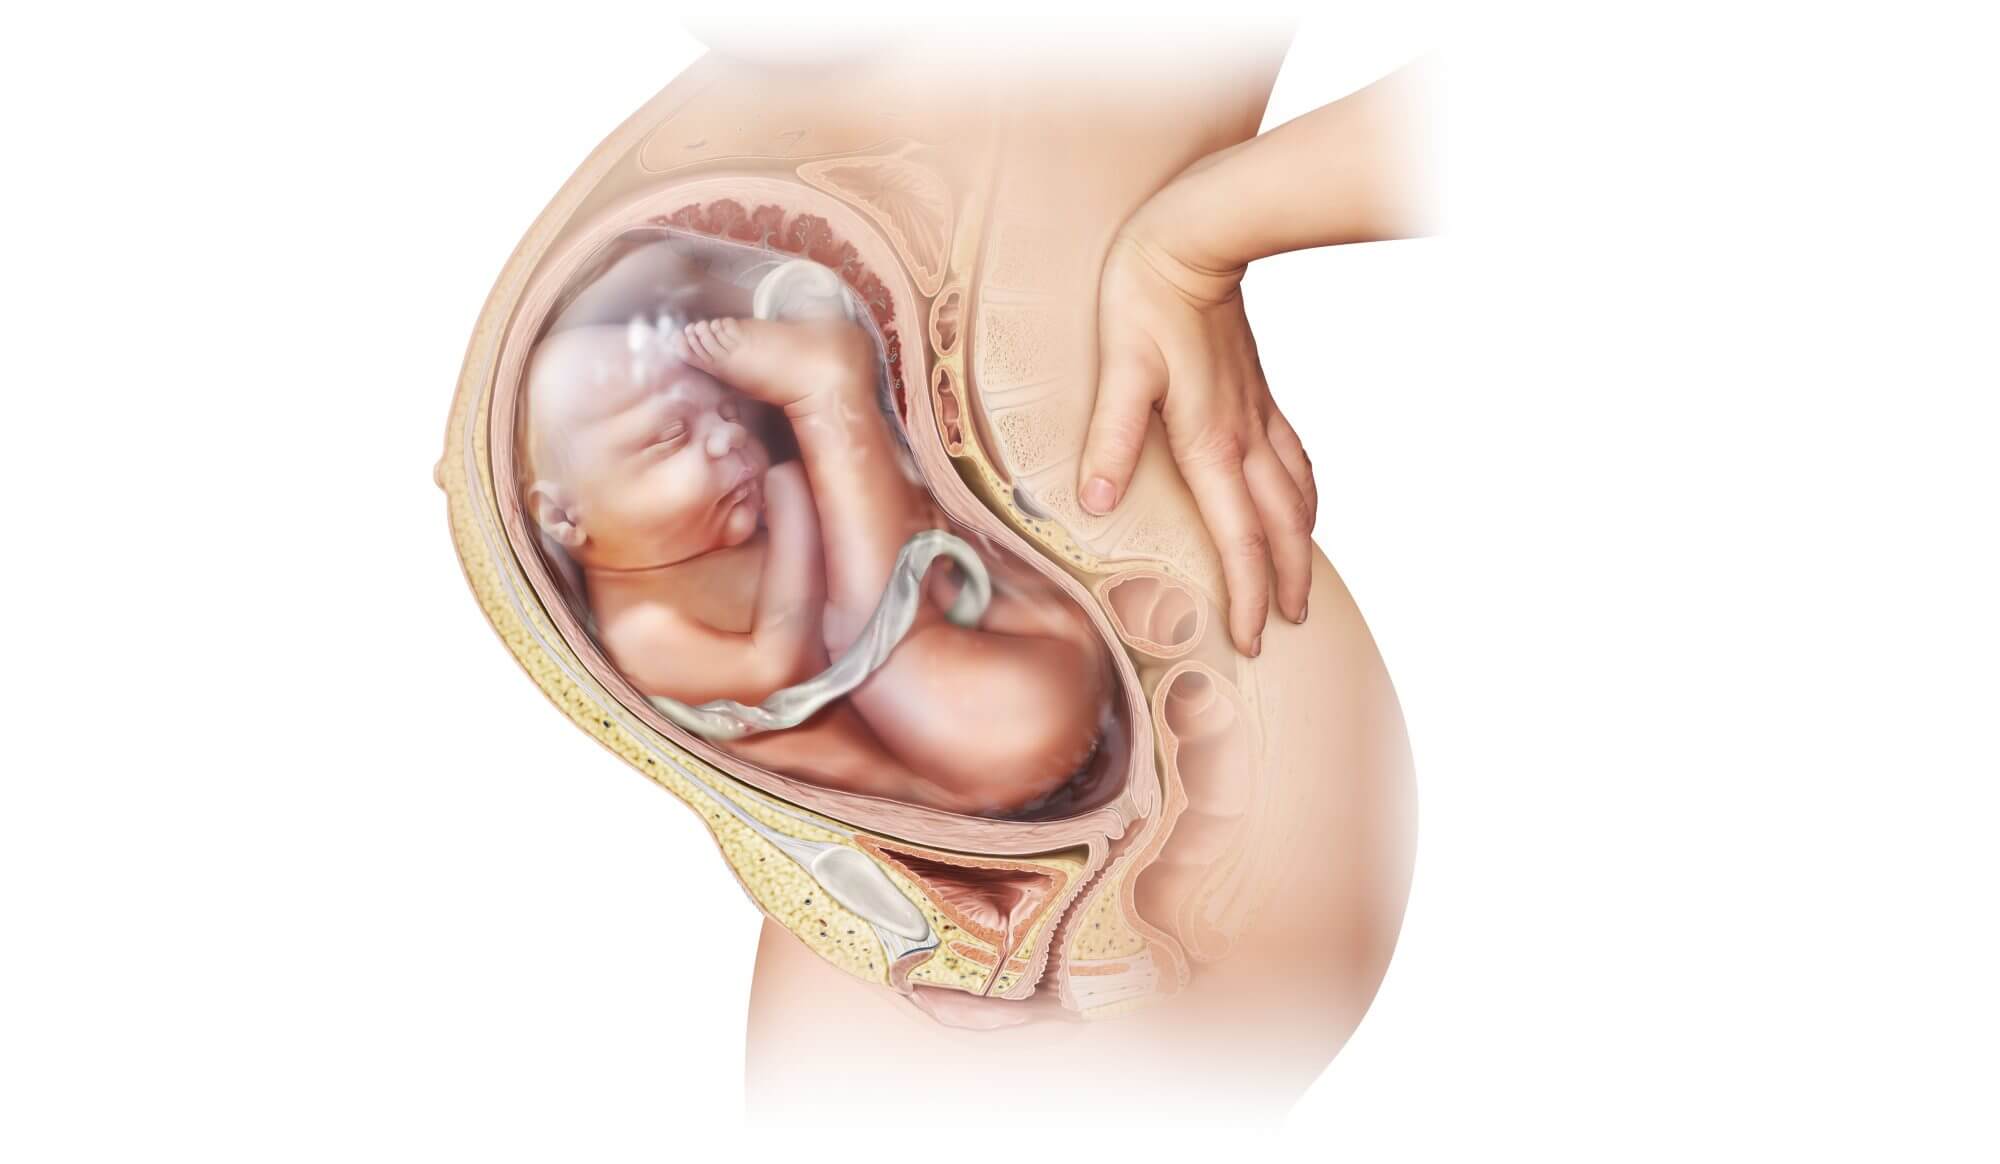

Околоплодный пузырь и плацента: структура и функции